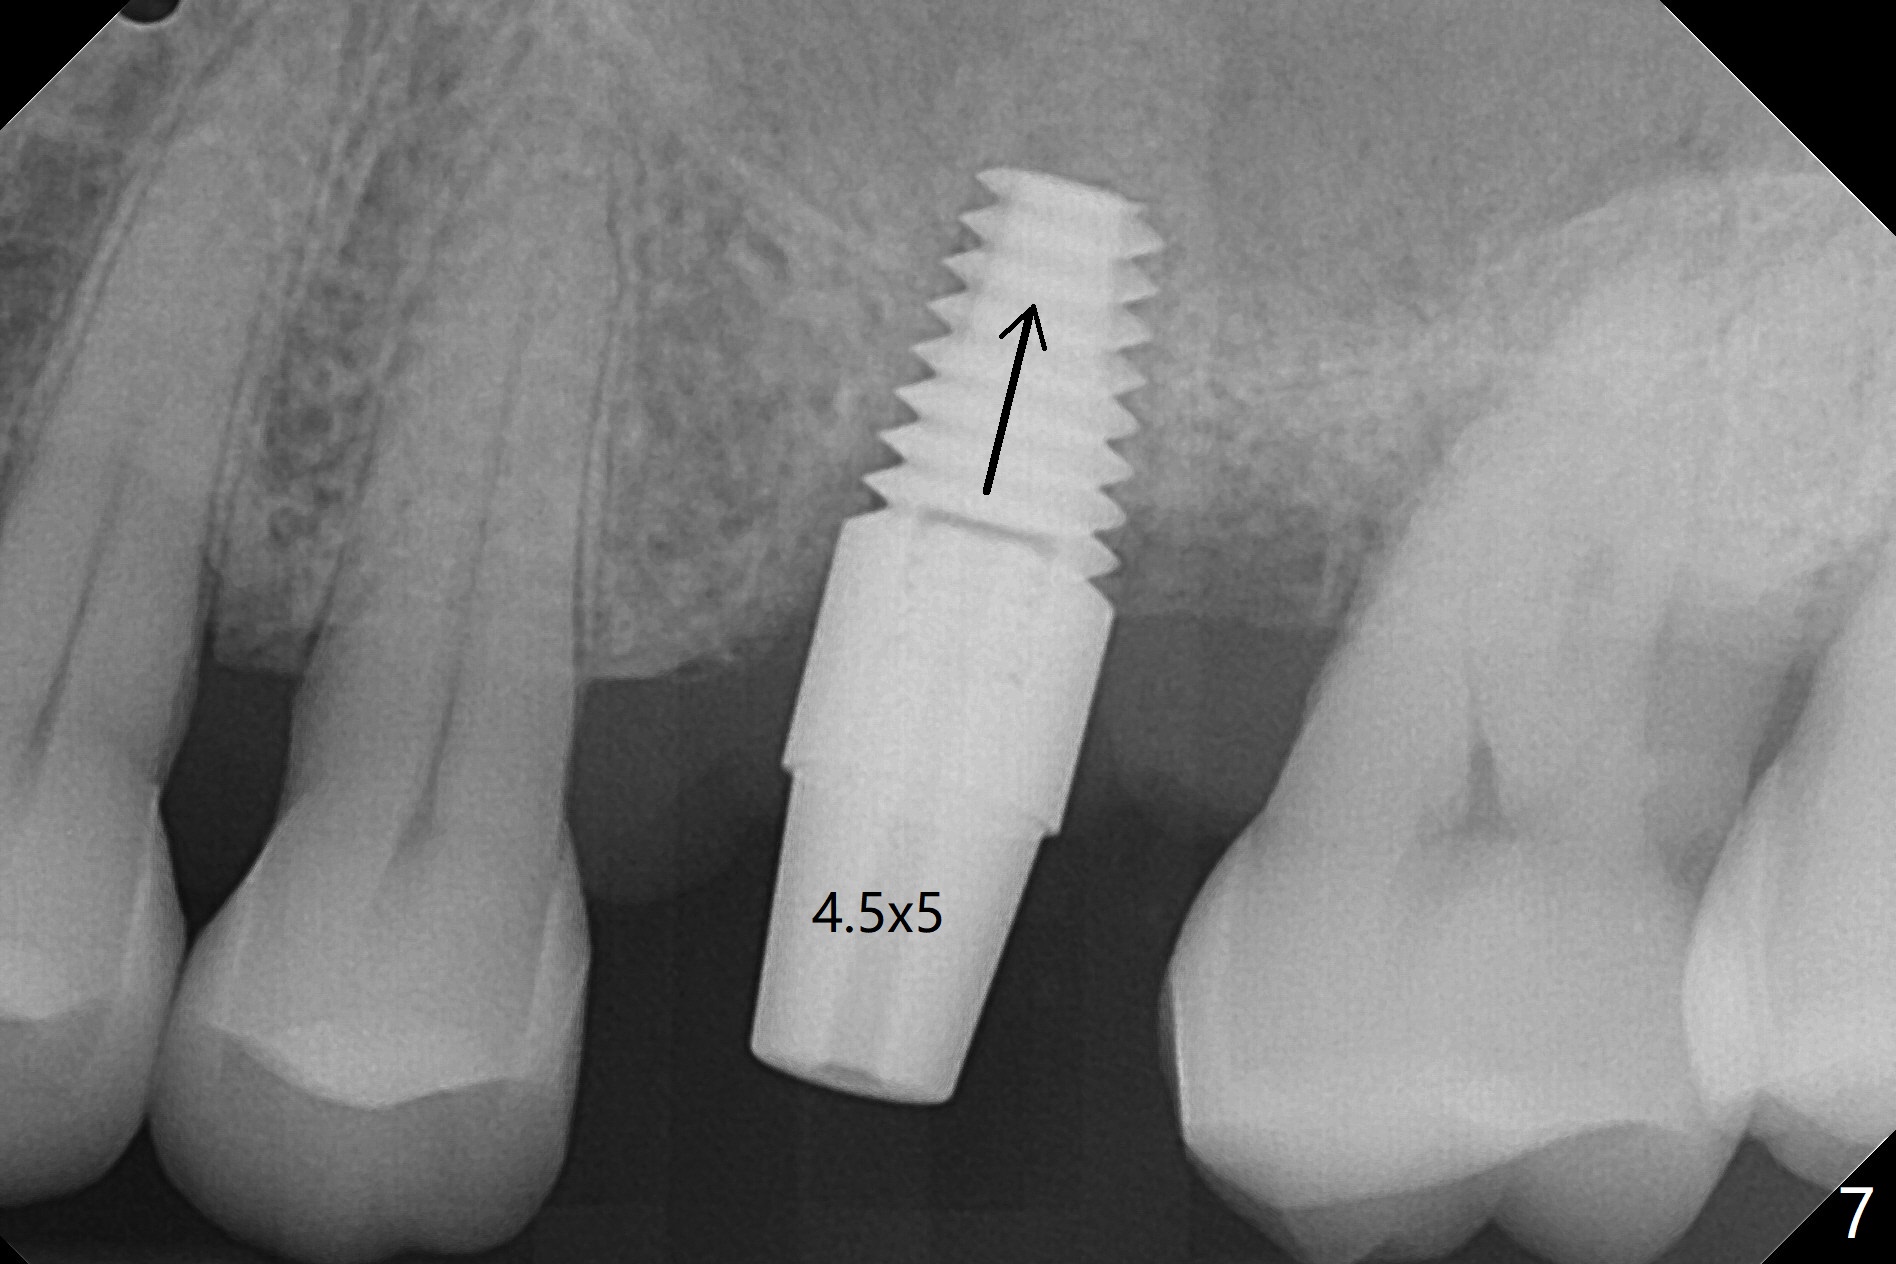

A 65-year-old man had crack tooth syndrome at #14 one month earlier (Fig.1). He shows up with crack and pain in an emergency manner (Fig.2 arrowheads). Preop CT confirms 4.5 mm bone height (Fig.3). Osteotomy will be initiated in the middle of the septum between 3 sockets (Fig.4). Depth of osteotomy is controlled with drill stoppers. After sequential osteotomy free hand, a 5x11 mm tap is used to break through the sinus floor (Fig.5) and sinus lift with Vanilla allograft. To prevent abutment screw loosening, a 5x11 mm tissue-level implant is placed; the distal thread is equicrestal (Fig.6 arrowhead). Following deeper placement of the implant (Fig.7 arrow) with a larger and longer abutment (as compared to that in Fig.6), the margin for an immediate provisional (Fig.9 white curved lines) is prepared in the coronal end of the implant (Fig.8 between arrowheads). With the tissue-level implant, the crown/implant ratio improves. Stress will be partially acting on the implant so that there is less likelihood of abutment screw loosening. The socket heals 1 month postop (Fig.10). The rough surface of the implant is exposed ~ 1 mm. With the margin modified and polished, the provisional returns to place with oral hygiene instruction. It is hoped that the gingiva will cover the exposed rough surface. The buccal rough surface remains exposed 5 months postop (Fig.11). The bone in sinus lift is mature 5 months postop (Fig.12,13). The first 1-2 implant threads are expected to be filled with mature bone in the near future (*). Since the abutment seems long enough for retention, temp bond is used for cementation (Fig.14). Water pik is being applied.